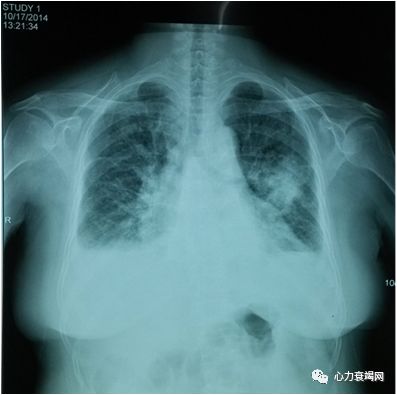

胸片:左肺中野团絮状高密度影,边界不清,双侧胸腔积液;